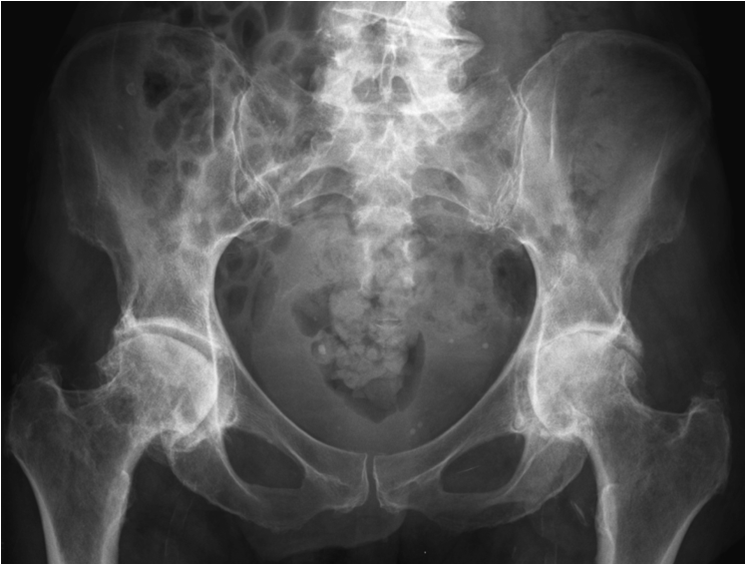

17.4. Degenerative Joint disease

Primary osteoarthritis involves weight bearing joints such as the knee, where changes are seen especially in the medial compartment and the patellofemoral compartment. In the hip changes are seen superolaterally. The tibiotalar joint is rarely significantly involved, except for changes along the anterior margin of the distal articular surface of the tibia. These are most likely posttraumatic in origin.

Fig. 13. A) Knee joint with degenerative changes. Note the sclerotic medial tibial plateau and joint space narrowing. A small osteophyte is seen on the medial femoral condyle. B.) Pelvis with marked degeneration of both hip joints. The right femoral head shows lateral osteophyte formation and is deformed. The joint space is narrow with increased subchondral sclerosis of the acetabular roof. The left hip has a marked joint space narrowing and lateral osteophyte formation. The femoral head shows increased density due to sclerotic areas and irregularity.